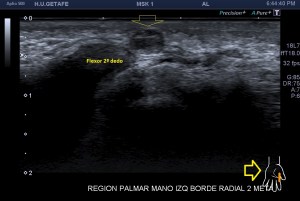

El paciente del caso que te expongo hoy como primer post del 2021 es un paciente de uno 40 años que nota desde hace un año un pequeño bultoma en la palma de la mano, en la región flexora en el eje largo del 2 dedo, a la altura de la articulación metacarpofalángica, ligeramente radial, viene referido del traumatólogo.

En mi interrogatorio habitual el paciente descarta traumatismo, no recuerda, ligero crecimiento sin dolor. Al tocar el bulto para localizarlo, lo primero que me llama la atención es que tiene pulso, muy evidente, es duro y muy pequeño, pero el pulso es muy evidente, no había coloración cutánea. El paciente ni el médico refirieron este dato superimportante (el latido) que dirigió el estudio absolutamente, como ves en la imágenes.

Escojo la sonda de ultraalta frecuencia, 18 mHz, y ajusto los parámetros para realizar un estudio con la intención de encontrar algo muy superficial, por supuesto, gran cantidad de gel, nada de presión, apoyo levemente el transductor.

1

En esta primera imagen me encuentro, primero, un estructura heterogénea, redonda, ligeramente ovalada con un centro anecoico y un halo grueso e hipoecogénico.

Lo segundo es delimitarla bien, tener bien estudiada la anatomía de referencia, imagen 2, respecto de la ecoestructura patológica y su propia ecoarquitectura. Por supuesto aplicamos el protocolo de referencia, localización, estudio, medición y vascularización que hoy ves resumido en estas 5 imágenes ya que el estudio lo enfoqué en el estudio de algo vascular.

2

La anatomía, tan importante siempre, buscando la relación, sobre todo, con el tendón al que claramente esta lesión no pertenecía ni afectaba.